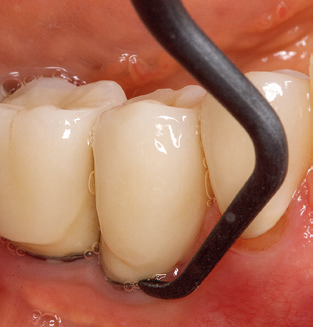

The current working concept for SPT

Updating the patient’s medical history is an important aspect of SPT and should occur at least once per year. It helps the dental team to identify and document any new risk factors. Especially when a patient is treated over many years, it is important to establish whether patient-specific and general health risk factors have changed. This primarily concerns a heightened risk as a result of diabetes, but other general conditions (cardiovascular disease and neoplasia) can also produce a modified risk profile as a result of the treatment performed and medication administered. Accordingly, updating the medical history as part of SPT is very important, as a modified risk profile may trigger the need to adapt the treatment interval. In the next step, it is important to afford the diagnostics due attention. Whilst instruments are a central aspect of SPT, findings and their documentation must never be neglected. The periodontological findings are essential for a good diagnosis; increases in the pocket depths and the BOP index are clear indicators of advancing periodontal and peri-implant disease. As such, the team should not shy away from probing implants too, with the aim of gathering the requisite data. At the same time, it is important to use periodontal probes with millimetre markings. Metallic probes have already been used for determining pocket depths around natural teeth for decades. In the case of implants, the challenge of recording correct and reproducible pockets depths is even greater. As the discrepancy between the implant diameter and the contour of the superstructure regularly results in overcontouring of the superstructure, flexible probes which still feature millimetre markings are a sensible solution for measuring pocket depths around implants (e.g., Colorvue Kit PCV11KIT6, Hu­Friedy; Fig. 4).

Fig. 4: Flexible probes with millimetre markings are recommended for the probing of dental implants (e.g. Colorvue Kit PCV11KIT6, Hu­Friedy). – Fig. 5a and b: A straight working tip (1P, W&H Dentalwerk Bürmoos GmbH) is a suitable instrument for use on all natural teeth. – Fig. 6: Curved working tips (3Pr/3Pl, W&H Dentalwerk Bürmoos GmbH) lend themselves to the processing of difficult-to-reach areas of the tooth and root surfaces (e.g. furcations). – Fig. 7: The tapered, hexagonal implant cleaning tip (1I, W&H Dentalwerk Bürmoos GmbH) permits atraumatic and efficient cleaning of the crown and abutment surfaces. – Fig. 8: Titanium and carbon curettes are suitable instruments for the manual cleaning of the implant surfaces.